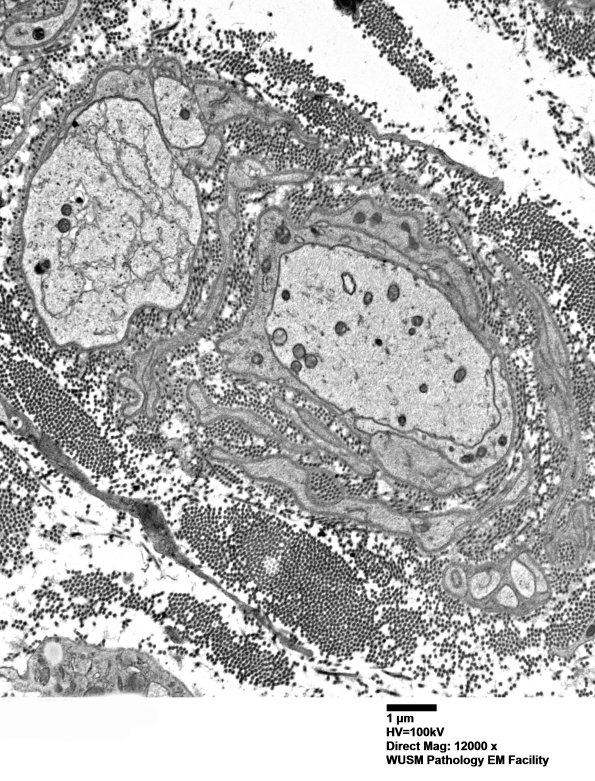

5B1-8 Ultrastructural examination confirms the loss of large and small axons and a population of naked demyelinated axons without evidence for remyelination. Macrophages are rare in the endoneurium and there is no evidence of macrophage mediated demyelination or increased myelin debris in endoneurial macrophages. Most Schwann cells do not contain myelin debris although pi granules are increased in some. ---- 5B1-5 Several demyelinated axons are shown at low and higher magnifications. (electron micrographs)